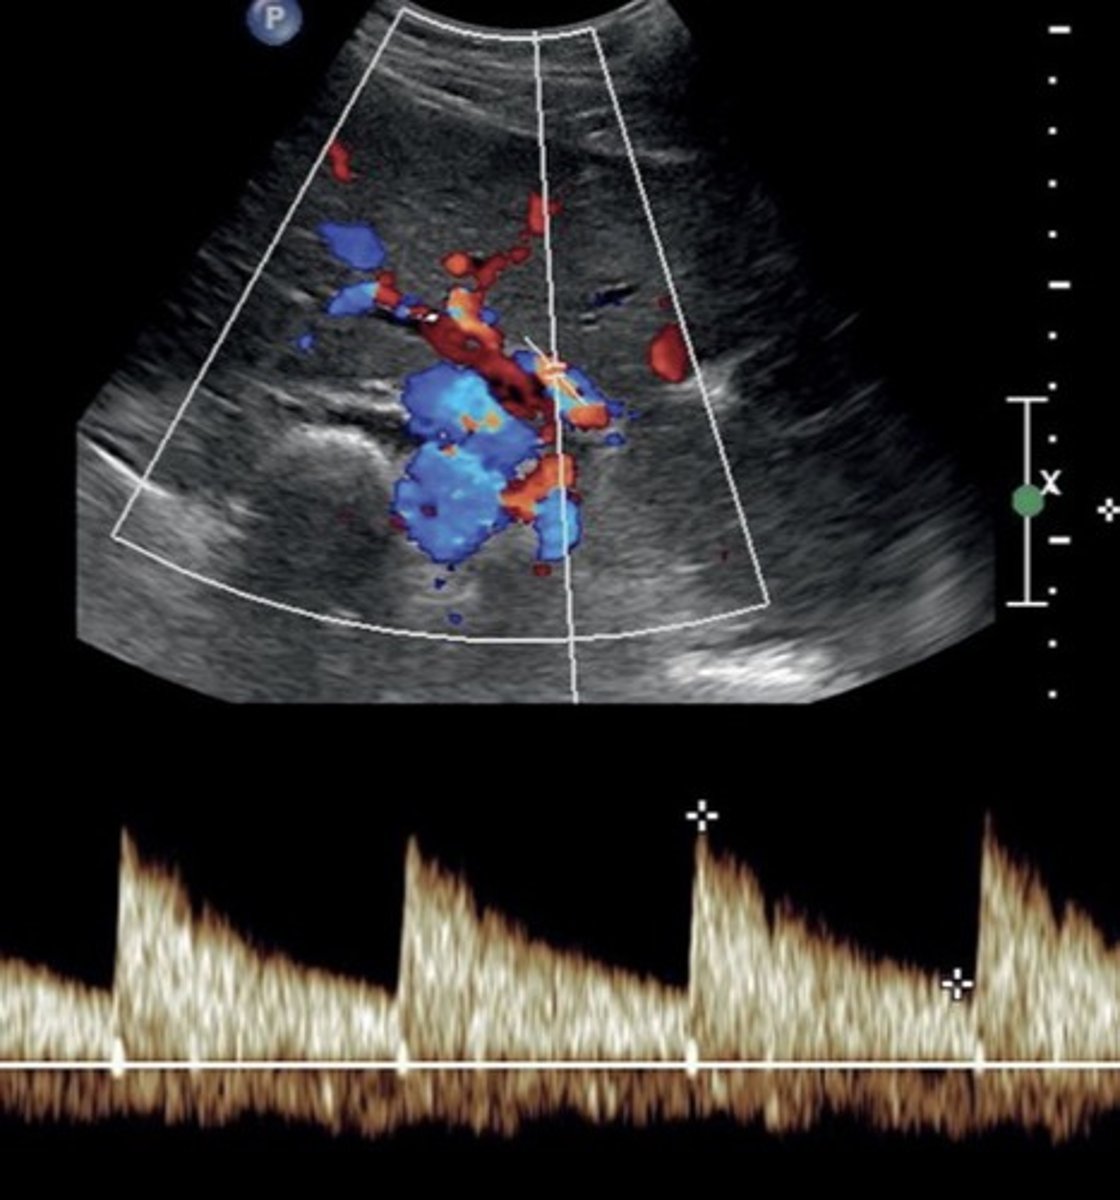

SMV Doppler Waveform

Hepatopetal flow

Continuous monophasic with slight respiratory variation